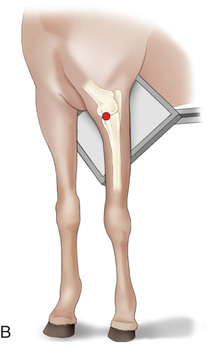

| Stifle | Lateromedial (LM) | Lateral (L) |

| Caudoproximal-craniodistal (CdPr-CrDi) | Caudocranial (CdCr) | |

Radiography of the femorotibial joint (stifle) is difficult because of the thickness of the surrounding tissue and the sensitive nature of this region. Because of the depth of the muscle in the femoral region, the caudocranial projection demonstrates little above the joint space. Radiographs of this region should be attempted only if the patient is cooperative. Safety is paramount in radiography of the hind region of the horse. Sedation or a twitch may be used; general anesthesia is also to be considered.